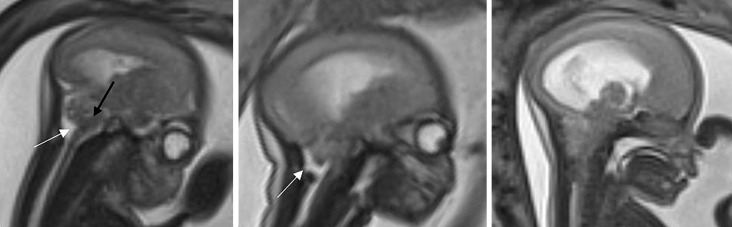

Results: This study included 71 fetuses with OSB for which 38 MRI examinations were analyzed; 61% (43/71) of lesions were MMC and 39% (28/71) were MS. Grade 3 (severe) Chiari II malformations were found in 80% (12/15) of MS and 43% (10/23) of MMC (p < 0.05). Fetuses with an atrial diameter less than 13.48 mm had a lower probability of requiring a CSF shunt at 12 months (p < 0.05). MMC was associated with a significantly higher frequency of clubfoot at birth (p < 0.05), whereas MS was significantly associated with more severe CHMII (p < 0.05). Although the correlations were not significant, we observed clear trends that more children with MS required shunts at 12 months and could walk at 30 months compared to children with MMC.